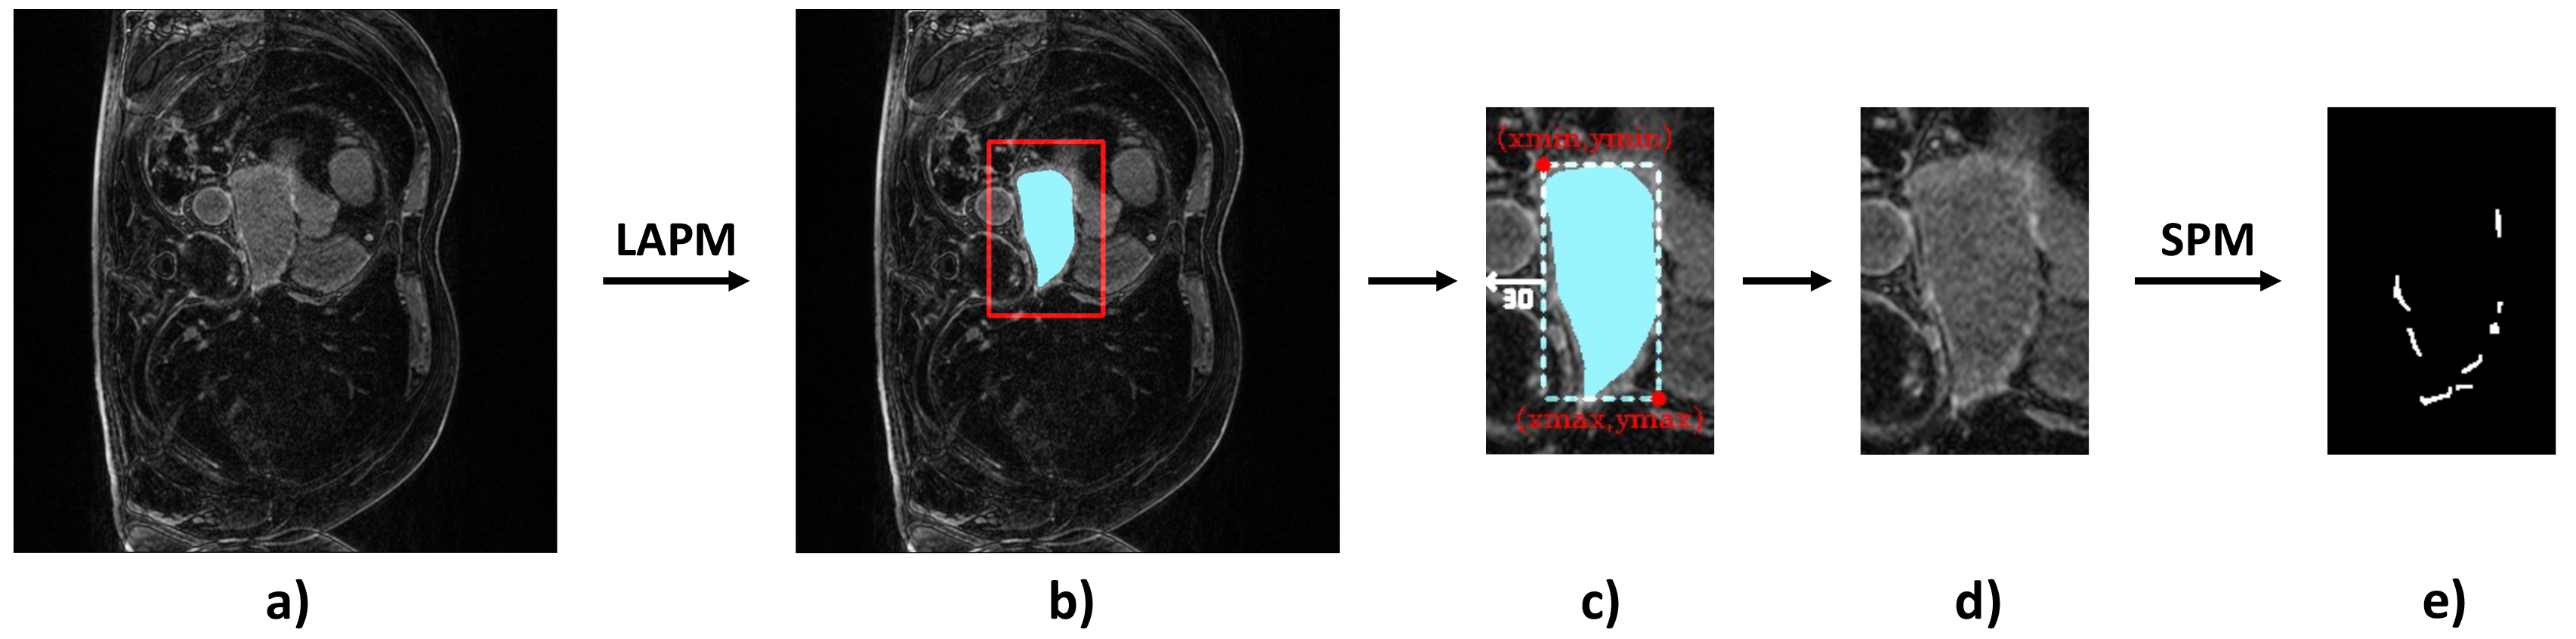

In terms of LA scar prediction, prior work predicts LA and LA scars separately without considering the relationship between them [16]. Meanwhile, the size of the scars is relatively insignificant, bringing difficulties in the prediction. Fortunately, LAs are much easier to be predicted, while LA scars are often detected near identified LA boundaries Fig. 2. Inspired by [29], we believe that combining the prediction of LAs and LA scars can be expected to improve scar segmentation performance.

We first trained the LA segmentation on task 2. The obtained model was loaded as the pre-training model for task 1. In detail, in the initial stage, the segmentation model was trained with all the LA labels available, obtaining the LA prediction model (LAPM). Then, we used the LAPM to roughly segment the targetted LA region, according to which images in the training set were cropped to train the scar prediction model (SPM). Specifically, the cropping region of interest (ROI) was implemented via , while , , , were boundary pixels of the predicted LA region, was an empirically-selected tolerance of LA prediction. Finally, the prediction map was restored to its original size using zero padding.

Figure 11 displays the prediction results with the two-stage prediction approaches and the normal ones. It can be clearly seen that the two stage method has successfully predicted most of the scars (see Fig. 11(c)), although some kind of false detection can still be observed. Nevertheless, with the common prediction method (see Fig. 11(f)), the scar is almost impossible to be predicted. We can hereby conclude that the two-stage prediction approach is essential in quantifying scars with irregular and tiny occupations on the picture.